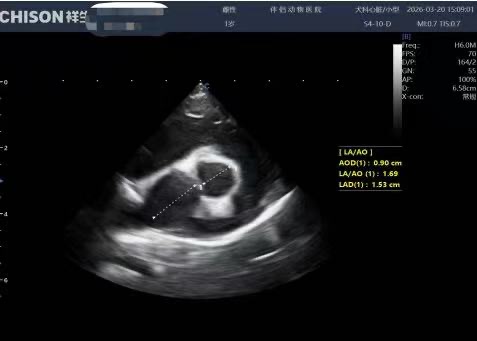

• 心脏超声

• 辅助检查:DR显示心脏轮廓增大、BNP检测数值显著升高;

• 最终确诊:二尖瓣腱索断裂,左心房轻度扩张